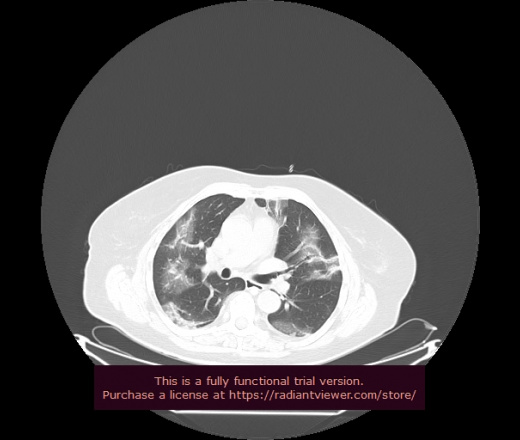

Уважаемые коллеги, если имеется интерес, сможете ли Вы спрогнозировать дальнейшее +-одинаковое течение процесса у 4 данных разных пациентов? Зацепиться где-то можно очень просто, где-то нельзя.